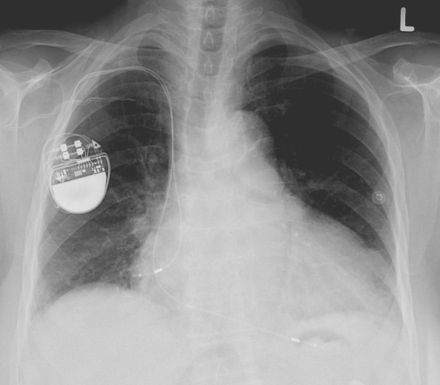

Pacemaker kan hackas och döda användaren Tillverkare får kritik för dålig säkerhet Forskare på den pågående säkerhets/hacking-konferensen Black Hat uppger att pacemakers från företaget Medtronic kan hackas och i värsta fall kan detta hota användarens liv. Enligt forskarna så krypteras inte trafiken när firmwaret på Medtronics pacemakers behöver uppdateras och detta gör det möjligt för obehöriga att installera malware i Medtronics pacemaker. På Black Hat-konferensen i Las Vegas demonstrerade de båda forskarna Billy Rios och Jonathan Butts hur man kunde hacka en maskin som läkare vanligtvis använder för att kontrollera patienters pacemakers efter de implanterats i patienter. Via den maskinen blev det sedan möjligt att installera programvara på pacemakers från Medtronics som i värsta fall skulle kunna göra så att pacemakern gav patienten livshotande stötar. De båda forskarna uppmärksammade Medtronics om säkerhetsproblemet i deras pacemakers redan i januari 2017 och de kritiserar nu företaget för att det fortfarande är möjligt att hacka deras maskiner. Tumnagel